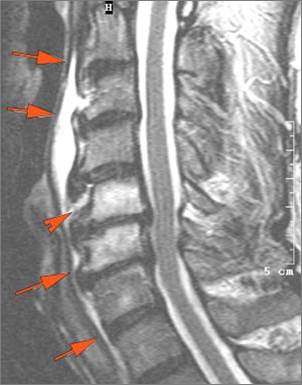

There is edema/abscess within in the prevertebral or paravertebral spaces. |

Yes | NA |

There is erosive process involving the disc spaces or other components of the spine. |

No | NA |

Pharyngitis with suppurative retropharyngeal adenitis.